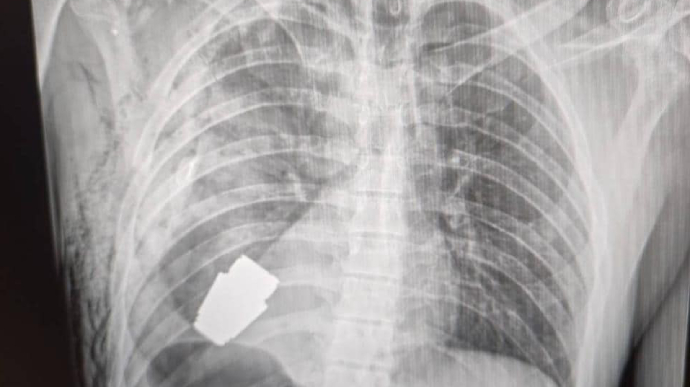

Українські лікарі під наглядом саперів провели унікальну операцію: видалили гранату ВОГ, що не розірвалася, з тіла військового.

"Не кожне поранення в області серця є смертельним! Військові лікарі провели операцію з видалення гранати ВОГ, яка не розірвалася, з тіла військовослужбовця, - пише вона. - Її було видалено у присутності двох саперів, які страхували безпеку медичного персоналу.

Операція проводилася одним з найдосвідченіших хірургів ЗСУ - Андрієм Вербою, без електрокоагуляції, оскільки граната могла детонувати у будь-який момент".

Оперативне втручання пройшло успішно, пораненого військовослужбовця відправили на подальшу реабілітацію та відновлення.